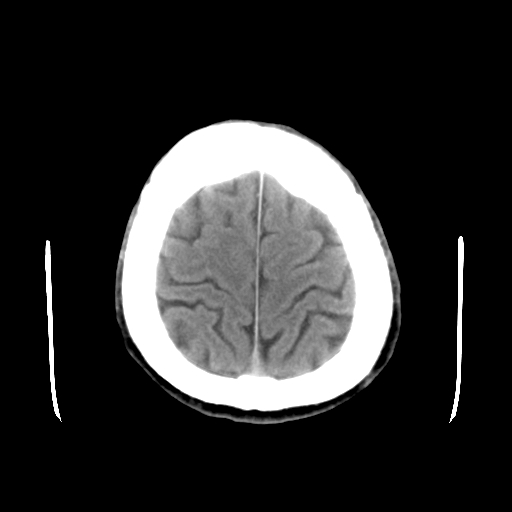

标题: CT15194:男,53岁,头痛、恶心三天。 [打印本页]

男,53岁,头痛、恶心三天。

筛窦囊肿、颅内未见明确异常